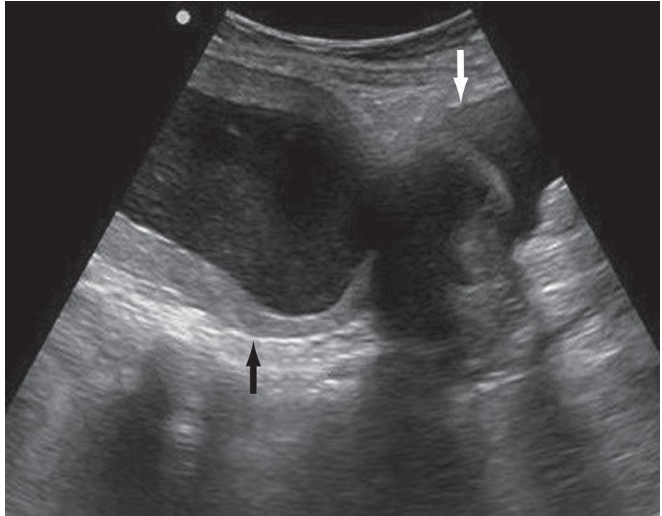

Sonographic Findings: The sonographic picture of large endometrial cavity fluid collections

is that of a centrally cystic, round, moderately enlarged uterus. This may contain echogenic

material if pus or blood is present.

Large Endometrial Fluid Collection